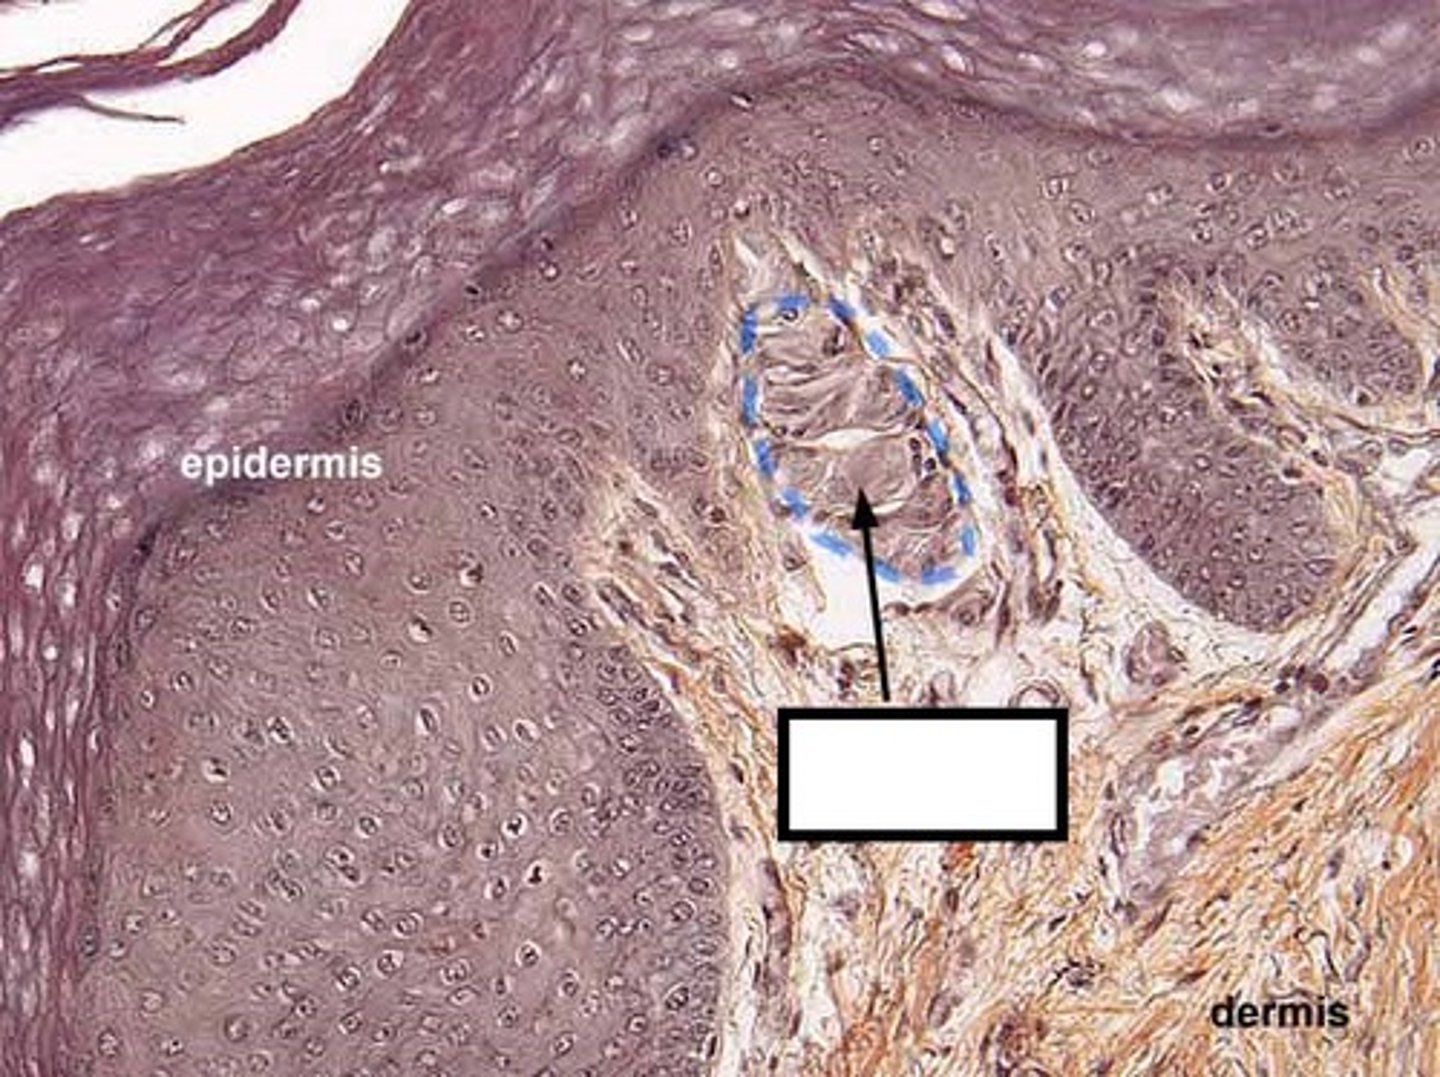

two components of cutaneous membrane

1) epidermis: superficial

2) dermis: deep

epidermis

superficial layer made of keratinized, stratified, squamous epithelium, avascular

dermis

- deep to epidermis and basement membrane

- made of loose connective tissue and dense irregular CT

- vascular

two layers of dermis

1) papillary layer

2) reticular layer

papillary layer

- thinner layer of dermis

- loose connective tissue

- collagen fibers are fond in this layer at the dermis-epidermal junction

- anchors dermis to epidermis

dermal papillae

- tiny projections in surface of papillary layer

- contains capillaries that allow oxygen to diffuse into ECF of dermis and then to avascular epidermis